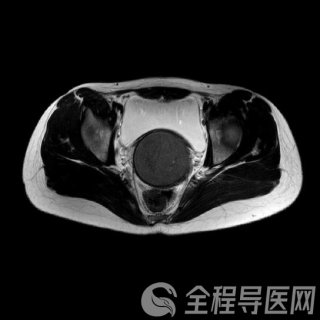

什么是多囊卵巢综合征

多囊卵巢综合征(PCOS)是青春期及育龄期妇女最常见的生殖轴内分泌紊乱性疾病,我国育龄期女性患病率约为5%~10%,在不排卵而导致不孕的患者中甚至占到30%~60%,是导致生育期女性月经紊乱和不孕最常见的原因。

临床上,以雄激素过高的临床(多毛、痤疮)或生化表现、持续性寡排卵或无排卵、卵巢多囊样改变为主要特点,经常跟“胰岛素抵抗”“肥胖”一起出现。